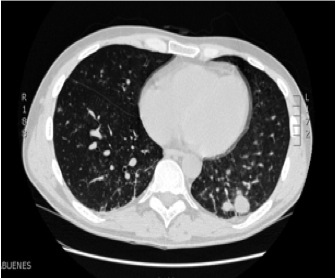

Lymphomatoid Granulomatosis of Central Nervous System and Lung Driven by Epstein Barr Virus Proliferation: Successful Treatment with Rituximab